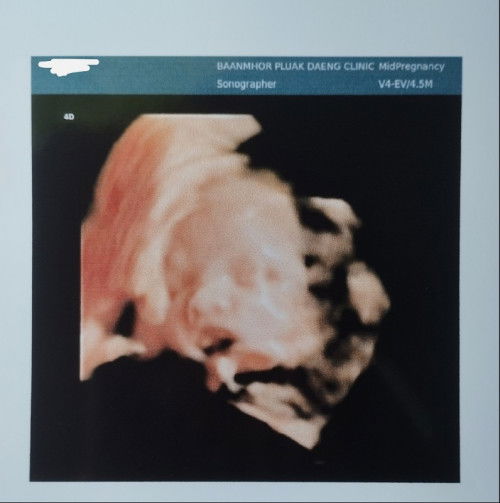

พอดีเรามีเลือดออกเลยไป รพ อายุครรภ์6week 6day โดยประมาณ ได้ซาวผ่านช่องคลอดดูถุงอยู่ในมดลูกถุงสวยดูปกติดีแต่ไม่เจอตัวเด็กหมอบอกน้องอาจะยังเล็กอีกอาทิตย์ให้มาซาวใหม่แอบกังวลค่ะแท้งมา2ท้องติดแล้วกลัวท้องลม🥺 #แม่ๆบ้านไหนมีภาพซาวด์ตอน6วีคมาแบ่งปันกันได้นะคะ อัพเดตค่ะ26/01/2023 เจอน้องแล้วค่ะอายุครรภ์7วีค1วัน อายุครรภ์ไม่ตรงกับประจำเดือนห่างกัน1สัปดาห์ค่ะ ได้ยินเสียงหัวใจแล้วค่ะดีใจมากๆ🥰 #แนบรูปให้อยู่ในภาพที่2นะคะ